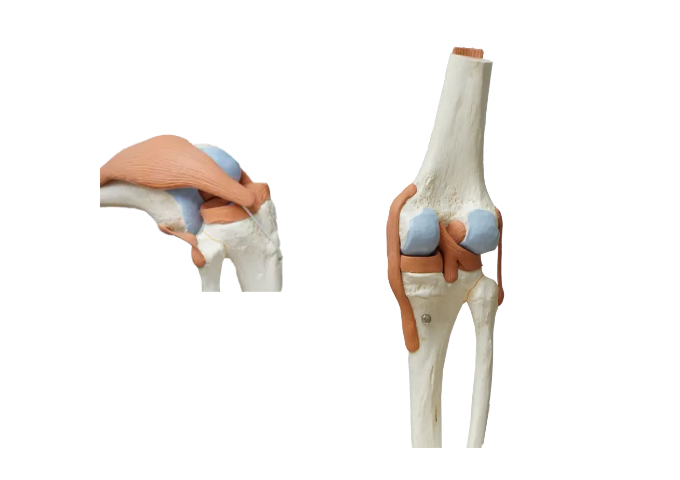

무릎에서 소리 나는 건 왜 그럴까

무릎 소리는 생각보다 흔한 현상입니다.

관절 안에서 공기가 터지거나, 힘줄이 움직이면서 나는 경우도 있습니다.

Q. 왜 40대 이후에 더 많이 생길까

나이가 들면서 연골이 조금씩 닳고

관절 주변 근육도 약해지기 때문입니다.